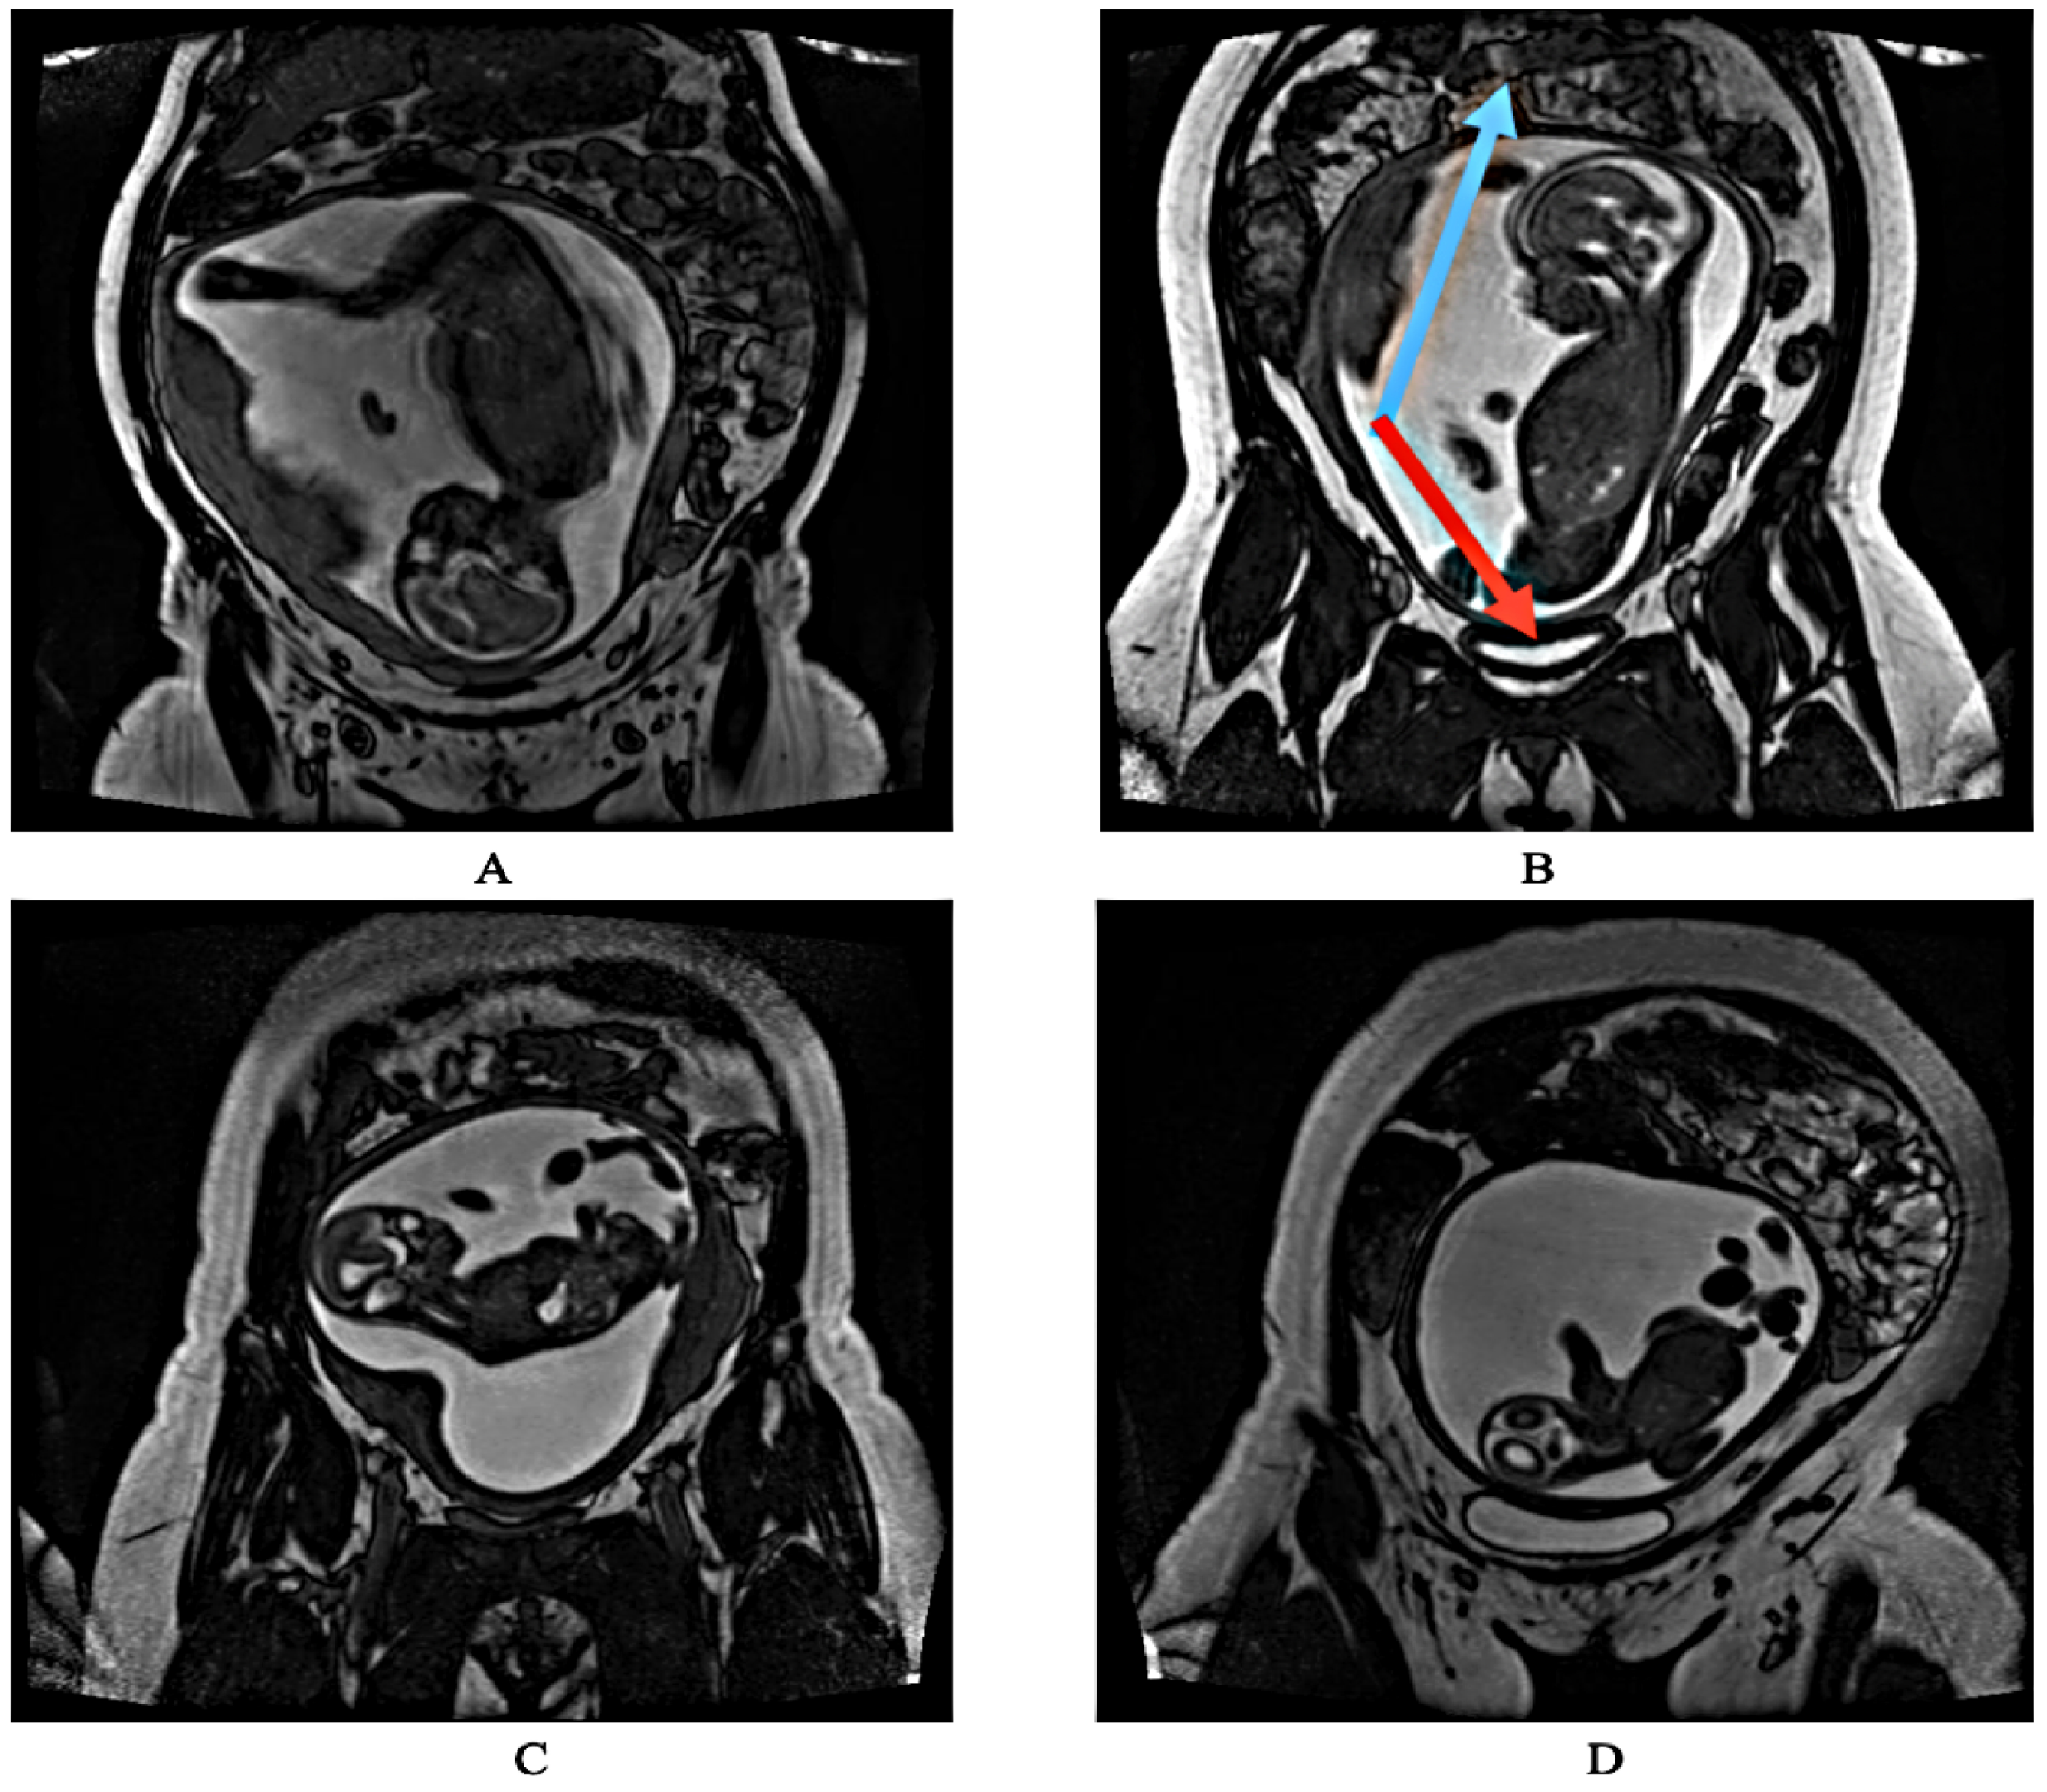

1. Introduction

2.1. Dataset